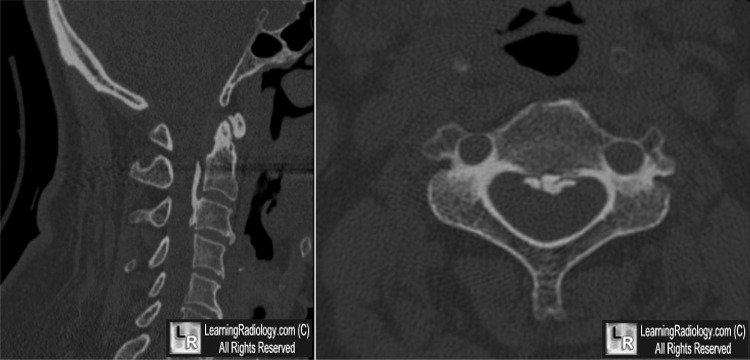

Ossification of the Posterior Longitudinal Ligament (OPLL). Above:Linear ossification just posterior to the posterior border of the cervical vertebral bodies (white arrows). Below: Sagittal reconstruction of cervical spine CT on left shows same flowing ossification (yellow arrow); axial CT demonstrates the ossified posterior longitudinal ligament (blue arrow).

- CT is best at demonstrating ossification

- Linear ossification immediately posterior to vertebral body in canal

- May be continuous (spans several bodies and intervening disc spaces), segmental (occupies back of body but spares disc spaces) or both